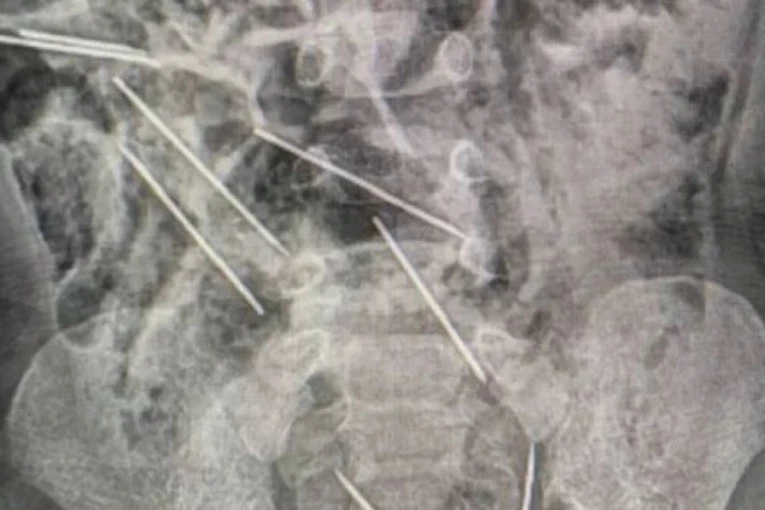

Dvogodišnji dečak koji je sredinom prošle nedelje progutao osam igala na severoistoku Perua konačno se nalazi van životne opasnosti.

Ispostavilo se da je u igri progutao čak osam igala od kojih su mu neke oštetile u telu organe, pa je osećao mučninu uz povraćanje.

- Tek kada smo ušli u operacionu salu i otvorili mu stomak, uočili smo prisustvo metalnih predmeta - rekao je doktor Efrain Salazar.

Doktori su posle operacije rekli da će morati da se prati njegovo stanje, jer nije sigurno da li su sve igle izvađene a oštećenja u telu sanirana.

Posle četiri dana dečak je morao ponovo na operacioni sto pošto mu se stanje pogoršalo.